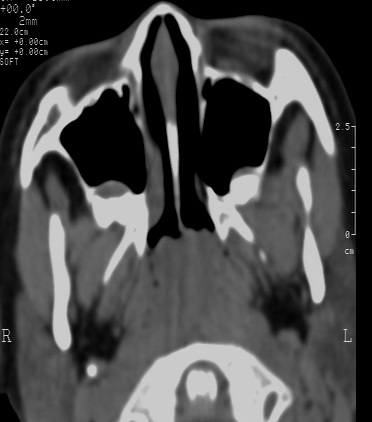

鼻咽腔顶壁及后壁软组织明显肿胀,厚度约2.5cm,鼻咽腔气道轻度狭窄,加之临床病史,支持腺样体肥大。

还可以用鼻咽侧位片测量鼻咽顶部增殖体的厚度和鼻咽腔的宽度,以两者比率来判断儿童增殖体是否肥大。正常时两者比率≤0.60;当比率为0.61~0.70属中度肥大;比率≥0.71属病理性肥大。